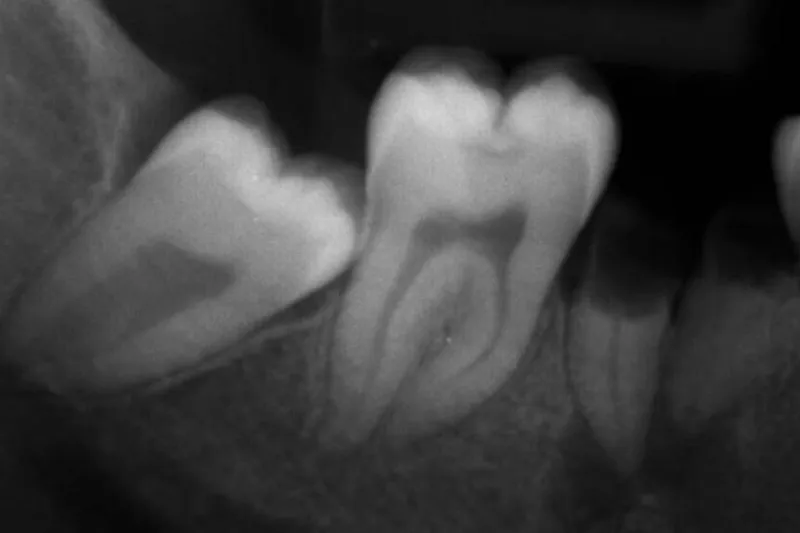

I studiet indgik 222 voksne personer, som alle deltog i et vedligeholdelsesprogram efter gennemført parodontalbehandling. Personerne havde ved undersøgelsesperiodens start 1.329 molarer, hvoraf godt halvdelen havde furkaturinvolvering af grad I, II eller III. Observationsperioden var mindst 10 år (12,4 ± 1,9 år).

Ved regressionsanalyse fandt man, at følgende patientrelaterede faktorer havde signifikant negativ indflydelse på overlevelsen af molarer: Alder > 50, hankøn, diabetes, rygning og manglende komplians. Tilsvarende negativ virkning blev påvist for en række odontologiske parametre: Gingival blødning, pochedybde ≥ 5 mm, furkaturinvolvering grad III samt manglende pulpavitalitet.

Forfatterne hæfter sig især ved den relativt dårlige prognose for avitale tænder og tænder med komplet furkaturinvolvering. De anbefaler, at man som kliniker inddrager forhold som rygning, diabetes og komplians i sine overvejelser om, hvorvidt man skal bevare eller ekstrahere molarer hos patienter med parodontitis.